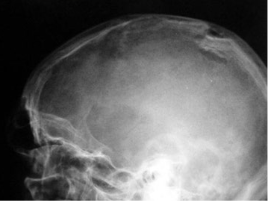

What fracture is this?

Depressed (Ping-pong)

Describe a depressed (ping-pong) fracture?

Skull fx where the fragment is depressed in like a ping pong ball